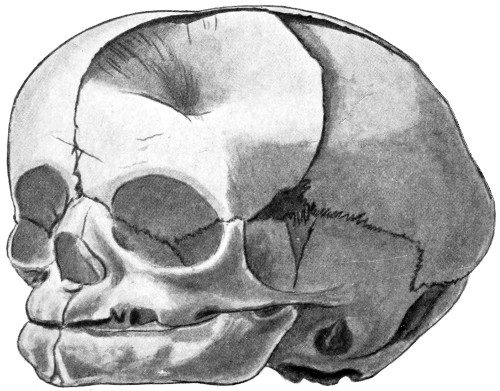

24 A and B. A case of depressed birth-fracture, before and after operation 47

25. To illustrate the effects and position of a birth-hæmorrhage 53

29 A and B. The base of the skull and the base as seen on transillumination 70, 71

30. Plan of the base of the skull 77